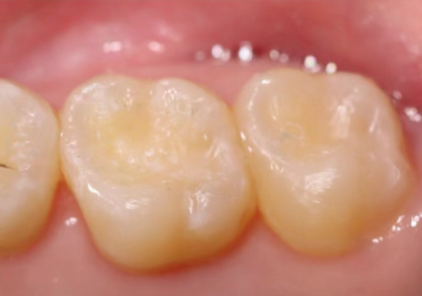

牙齿美白价格大概多少左右?揭晓真实费用与效果对比! 文章围绕牙齿美白价格展开,指出其受牙齿状况、地区、口腔机构等因素影响。普通黄牙美白费用2000 - 3000元,含洗牙抛光和冷光美白,效果维持约2年;严重黄牙(四环素牙等)常需贴面修复,一颗2500 - 6000元,整体费用较高。建议普通黄牙选冷光美白,严重黄牙且预算足选贴面修复,要选正规机构。 牙齿美白 2026年03月04日 0 点赞 0 评论 7 浏览